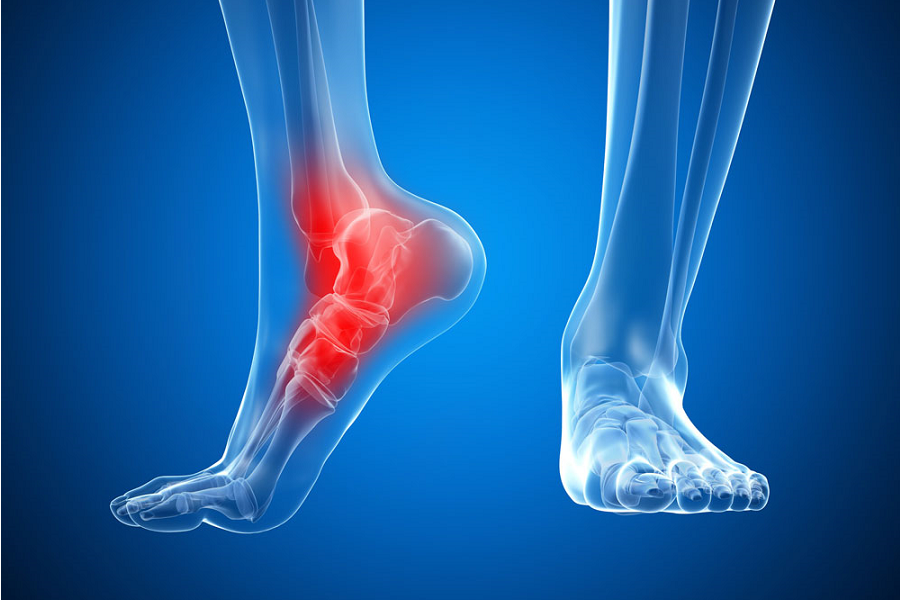

Подавляющее большинство травм голеностопного сустава связано с растяжением связок, поддерживающих этот сустав. Чаще всего происходит растяжение связок латеральной лодыжки – дистального отдела малоберцовой кости, выступающего в роли стабилизатора голеностопного сустава. Растяжение связок голеностопного сустава обычно происходит при чрезмерной инверсии стопы (подъёма внутреннего края стопы в тыльном направлении).

При чрезмерной инверсии стопы возможно повреждение связок латеральной лодыжки – подобное растяжение считается одной из самых распространённых травм мягких тканей нижних конечностей. Строение ноги и костей стопы, равно как и сравнительно небольшой размер данных связок делают их крайне уязвимыми для растяжения.

Основная функция связок латеральной лодыжки заключается в ограничении чрезмерной инверсии стопы. Несмотря на их важную роль, эти связки не так сильны и эластичны, как те, что расположены с противоположной стороны голеностопного сустава. Именно поэтому растяжения связок голеностопного сустава вследствие чрезмерной инверсии встречаются чаще, чем растяжения, связанные с чрезмерной эверсией (поворотом внутреннего края стопы в подошвенном направлении).

Связочный комплекс латеральной лодыжки включает в себя три основные связки. Точки их прикрепления достаточно просто обнаружить, поскольку названия этих связок указывают на две кости, соединённые ими. Три ключевых связки латеральной лодыжки – передняя таранно-малоберцовая связка (соединяет таранную кость и малоберцовую кость), задняя таранно-малоберцовая связка (также соединяет таранную и малоберцовую кости), и пяточно-малоберцовая связка (соединяет пяточную кость и малоберцовую кость). При чрезмерной инверсии стопы чаще всего происходит растяжение передней таранно-малоберцовой и/или пяточно-малоберцовой связок. (Рис.1).